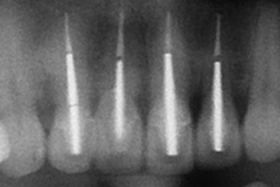

舊牙冠拆除後,術後X光片。

治療後,X光片。